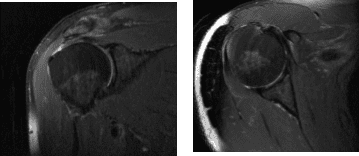

The patient presented MRI results that have shown small full-thickness tear of the distal supraspinatus tendon at its insertion measures 1.3 x 1.5 cm. Background tendinosis and attrition of the torn supraspinatus tendon. Tendinosis of the superior distal subscapularis tendon.

No rotator cuff muscle atrophy. Mild tendinosis, intra-articular long head of the biceps tendon with mild tenosynovitis. Tear of the posterosuperior labrum. Small subacromial subdeltoid bursitis communicates freely with small joint effusion. Mild osteoarthritis of the AC joint.

MRI Right Shoulder Non-contrast